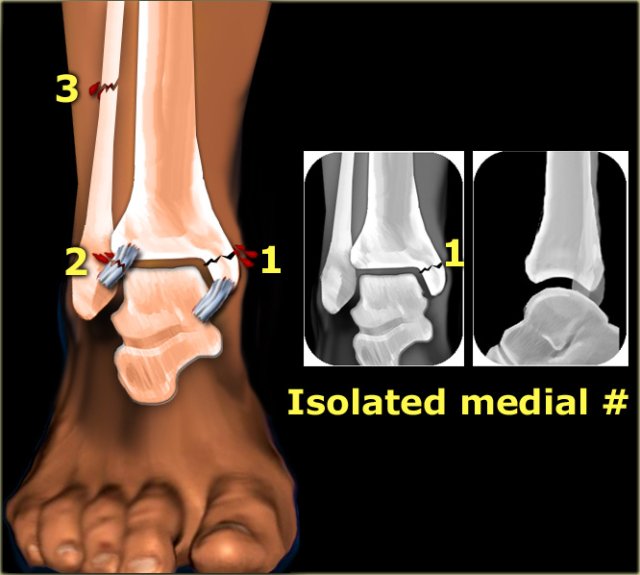

1. Isolated fracture of the medial malleolus

2. Isolated fracture of the posterior malleolus without a fracture on the lateral side

3. Any painful swelling or hematoma on the medial side without a fracture on the radiographs

Isolated fracture of the medial malleolus

According to Lauge-Hansen this is the first stage of a pronation exorotation injury, which results in a Weber C fracture.

So we have to look for higher stages.

The injury can continue to the following:

• stage 2: rupture of the anterior syndesmosis

• stage 3: high fibular fracture

• stage 4: rupture of the posterior syndesmosis

In all these subsequent stages, purely ligamentous injury will not be visible on the radiographs of the ankle.

So even in a Weber C stage 4 sometimes only a fracture of the medial malleolus will be visible.

In the illustration we see the fractures and ligamentous injury on the left and the resulting x-rays on the right.